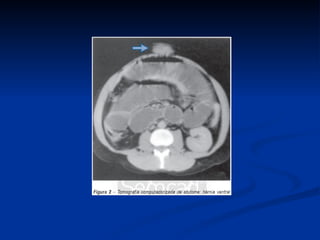

Diagnóstico Radiológico